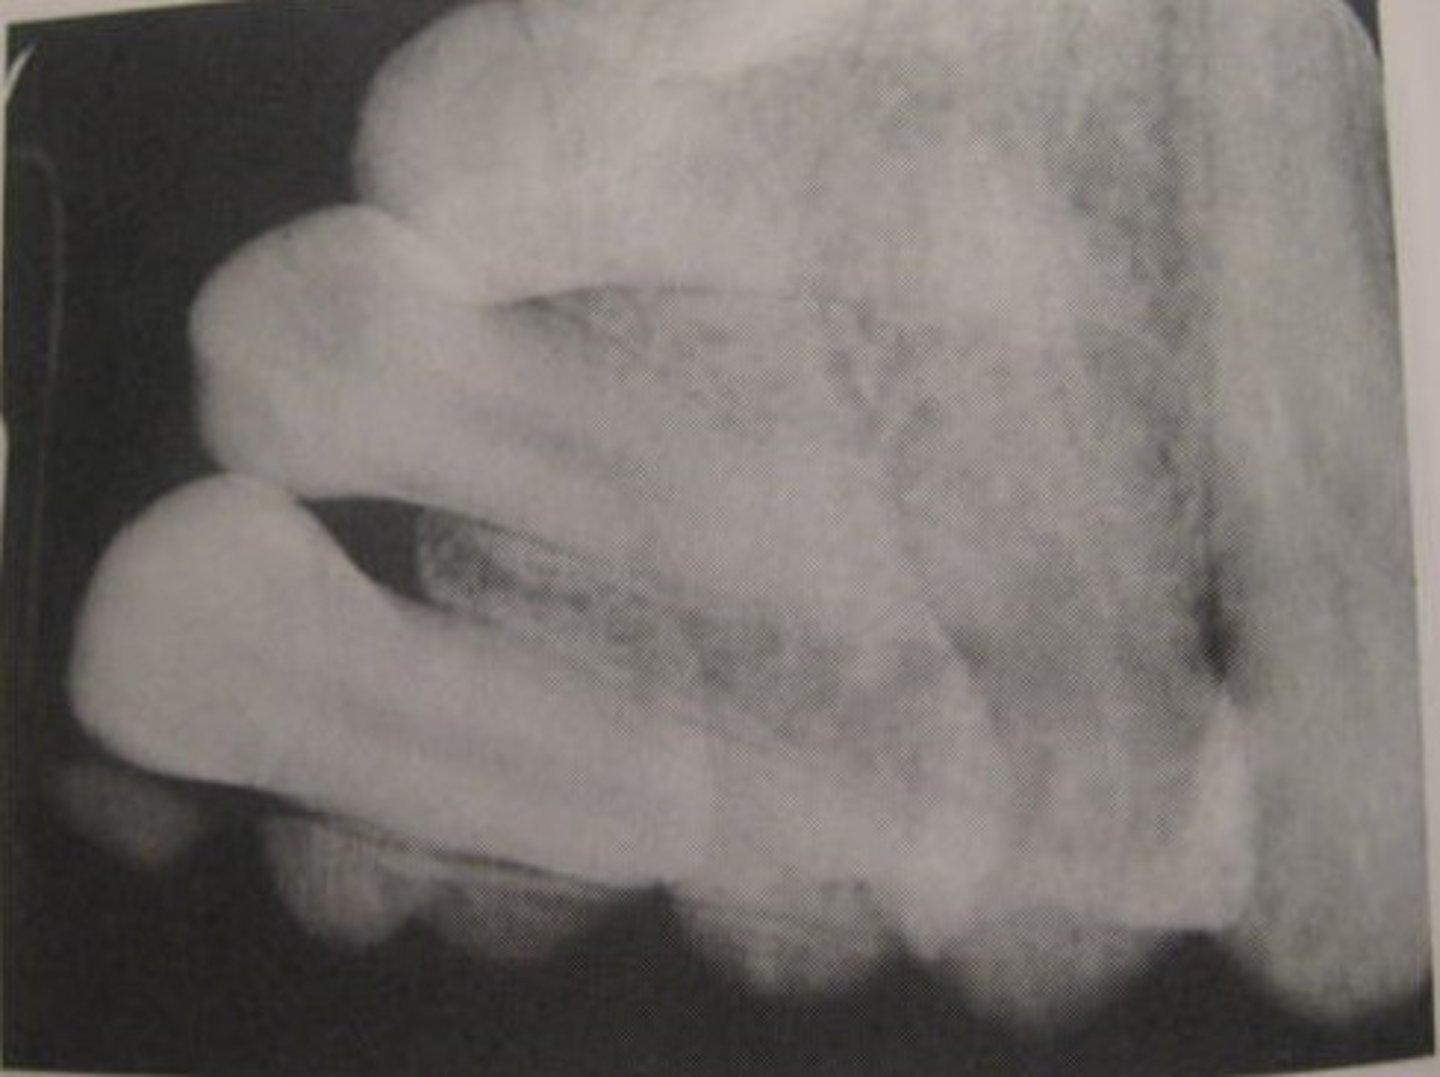

What causes elongation (longer crowns and roots) on an image?

Insufficient vertical angulation.